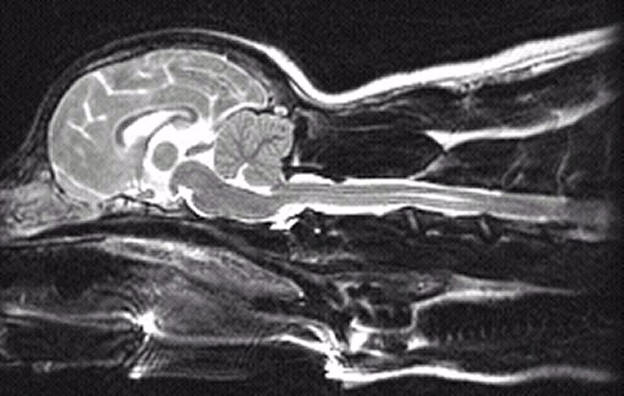

3 years old

No symptoms of SM

Mild malformation, slight

squashing/pinching of cerebellum

Probable mild dilatation of the central

canal

Medulla kinked/squashed

You can also see the vertebrae. They are the white lines that look almost like pointers

underneath the spinal cord. Three are visible.

One (C1) is below the cerebellum where

the spinal cord begins

The other two are further back--C2 and C3